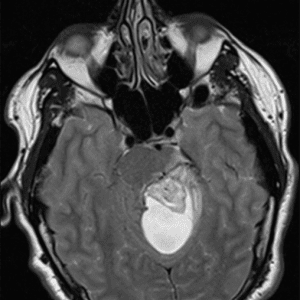

U nguyên bào mạch máu

Lượt xem: 220» 19-06-2020 -